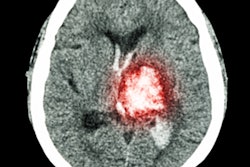

The patient, Ben Littlewood, underwent a brain CT scan at Tameside Hospital soon after his mother found him unconscious and seizing on the kitchen floor. The consultant radiologist who read the initial CT scan, Dr. Shiva Koteeswaran, reported that the scan appeared "completely normal."

It wasn't until Littlewood underwent a follow-up CT scan four days later that the healthcare providers realized he had experienced an ischemic stroke due to basilar artery thrombosis, at which point no realistic treatment options remained.